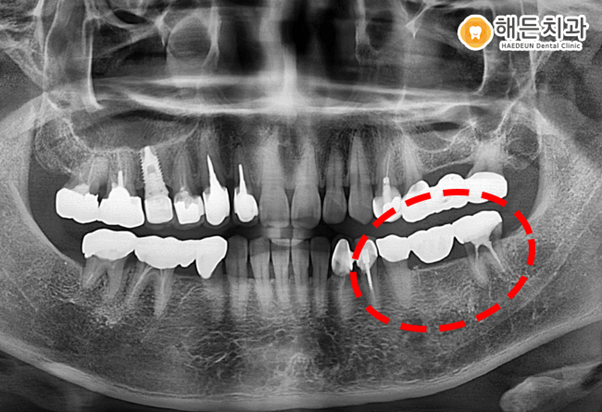

위 사진은 아산시충치치료 해든치과에 내원하신 김*향님의 님의 치아 사진입니다.

환자분께서는 왼쪽 아래 금으로 떼운 부분이 떨어진 건지 체크를 받고 싶다고 본원에 내원 해주셨습니다.

과거에 왼쪽 아래 치아들은 브릿지로 덮어 씌워 놓은 상태였는데요.

상태가 좋지 않아 왼쪽 아래 브릿지를 제거해보니 맨 후방의 어금니는 더 이상 살리지 못해 발치를 해야 하는 상태였습니다.

작은 어금니는 일단 살려 보기로 했습니다.